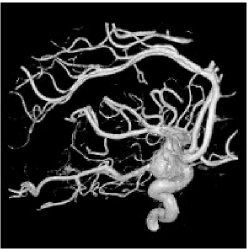

4.2 Inhomogeneous image segmentation

In this subsection, we extend our proposed method to segment two classes of inhomogeneous images shown in Figure 4.6. The left is a synthesized image by combining the arterial blood vessels of a human head. The right is a MRI brain image based on an anatomical model of normal brain from the slice 91 of the normal brain database, which is available to the public at http://www.bic.mni.mcgill.ca/brainweb/. Here we set as “modality=T1, Slice thickness=1mm, intensity non-uniformity = 20%” for the original image 4.6(b). Different to the numerical comparisons of the piecewise constant image, we do not know the real segmentation due to the inhomogeneity. So we except to obtain a better restored image as the stopping condition in the first step of our proposed strategy.

Refer to caption

(a) Synthesis Image

(b) MRI Image

Figure 4.6: The original images in Example 4.3 and 4.4.